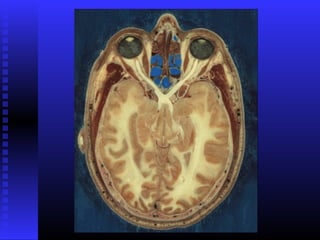

 IRREGULARESIRREGULARES

IRREGULARESIRREGULARES